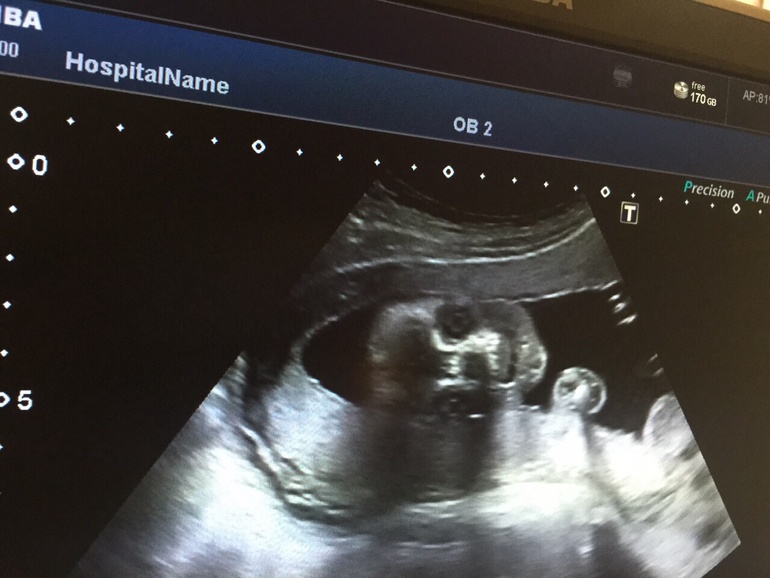

Во время УЗИ на мою просьбу сделать фото врач сообщила, что принтер у них совсем плохой; на просьбу сфоткать малыша на телефон с экрана, - что аппарат вообще плохой, хороший забрали, и что изображение такое, что только им понятно, и мне нечего там смотреть...

Однако, самое главное все же - здоровье! И здесь у нас все в порядке! :)))) Все органы ребеночка хорошо просматриваются, все параметры соответствуют сроку; количество вод нормальное. Расположен головкой вниз, что меня очень радует :)))) Врач сказала, что врядли уже перевернётся. Вес малыша, как сказали, 1919 грамм.